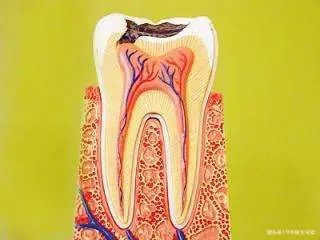

至于牙髓炎,相信大家都知道,这个病就是牙髓组织的牙髓炎的炎症。牙髓是由于神经血管结缔组织,牙髓的位置在牙齿内部的牙髓腔内。牙齿硬组织疾病如果得不到及时有效的控制和治疗,很可能会引发牙髓炎,成为口腔最常见的疾病之一。那么,你知道如何正确区分牙髓炎吗?下面给大家介绍一下鉴别牙髓炎的方法。1.牙髓炎的症状1。深龋、可逆性牙髓炎、慢性牙髓炎(1)有疼痛症状时可有冷热痛,但深龋、可逆性牙髓炎的牙齿无自发性疼痛史;慢性牙髓炎可有自发性疼痛史。

其实牙髓炎这种病是有一定原因的,是上火引起的,因为上火会导致身体各项功能的下降,为病毒感染创造了一定的环境。日常生活中,引起牙髓炎的因素比较复杂,牙髓炎的具体因素需要和专家做好沟通。1.牙髓炎的原因(1)牙髓炎疾病的形成主要是由于感染。任何病毒侵入人体后,都会对身体造成一定的伤害。任何原因引起的细菌及其毒素都会侵入髓腔,引起牙髓的炎症。

慢性牙髓炎患者会反复发作,患者时不时出现牙痛症状,牙龈红肿疼痛,尤其是上火发生后,会导致病情发作。那么,慢性牙髓炎能自愈吗?1、无法自愈(1)慢性牙髓炎是一种比较常见的牙病,以疼痛为主要症状,有时会出现剧烈的难以忍受的疼痛,常使患者感到事事不舒服,主要是由于牙齿感染。龋齿、缺损等牙齿硬组织疾病,如果得不到及时有效的控制和治疗,可能会导致牙髓炎,所以牙髓炎是口腔中最常见、最常见的疾病之一,是无法自愈的。